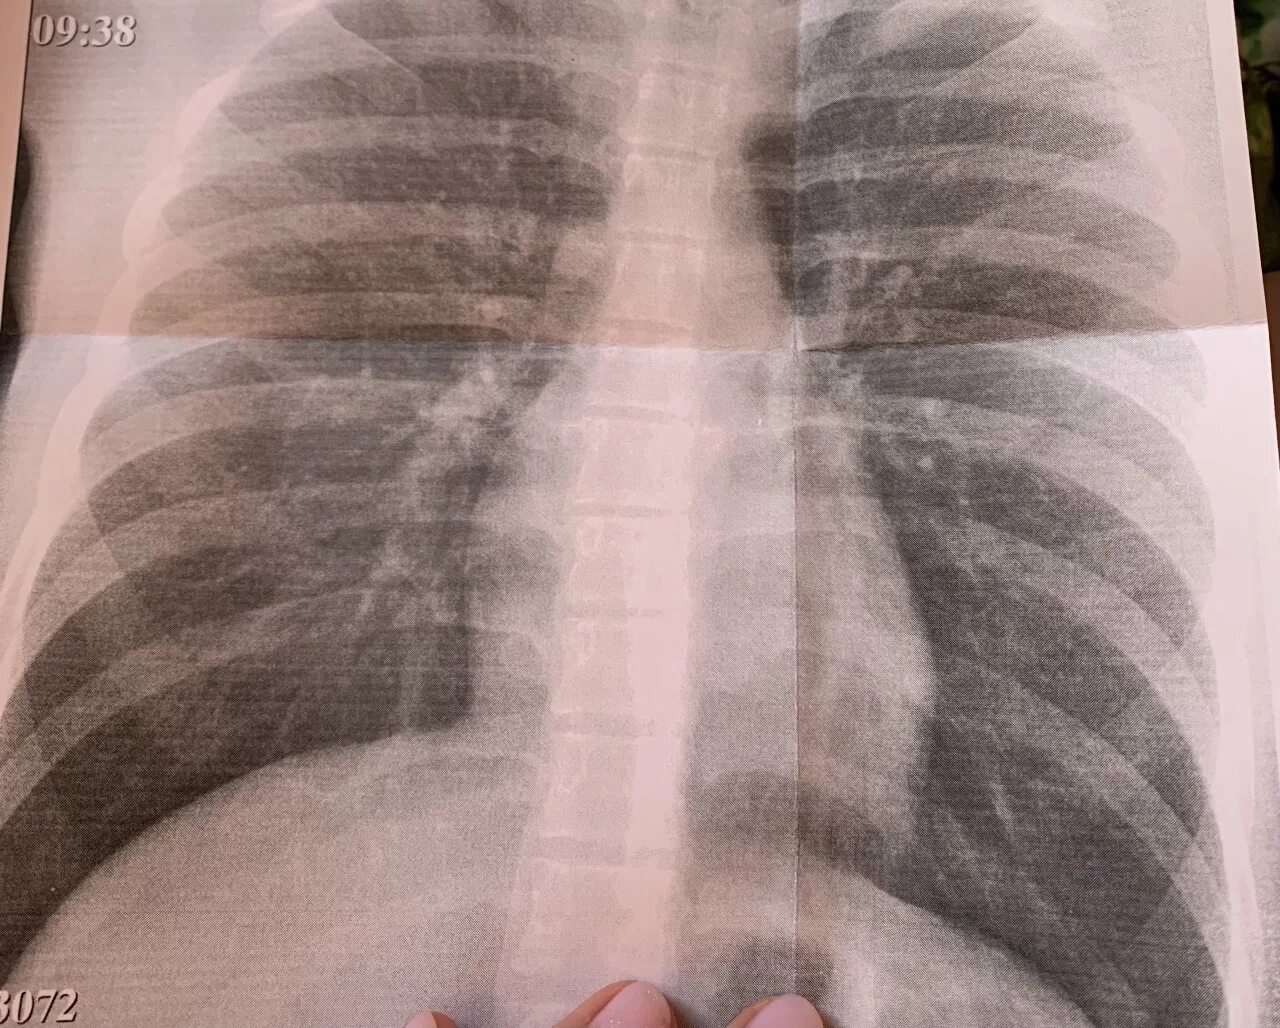

Пятно в легком что это может быть